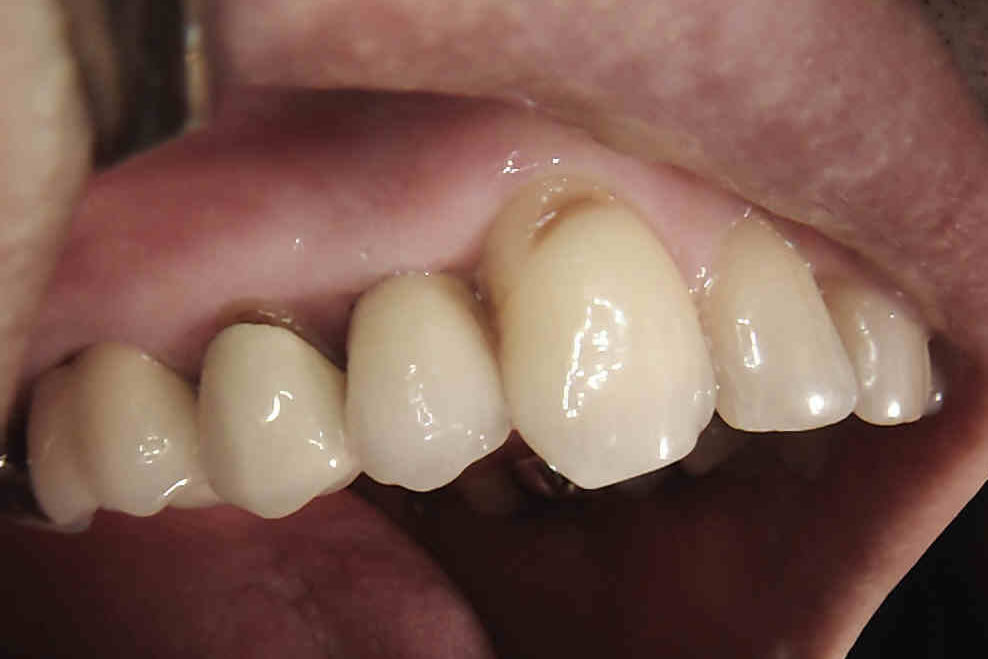

IMPLANTS FOR SINGLE & MULTIPLE MISSING TEETH

Dental implants are the best-known treatment to replace single or multiple missing teeth because they feel and behave just like natural teeth. After a while you won’t be able to tell the difference – even forgetting that they are there.

The procedure to place implants and replace a missing tooth or multiple teeth is straightforward as there is little need to treat surrounding teeth. Once a crown is placed over the implant it will appear indistinguishable from the natural teeth.